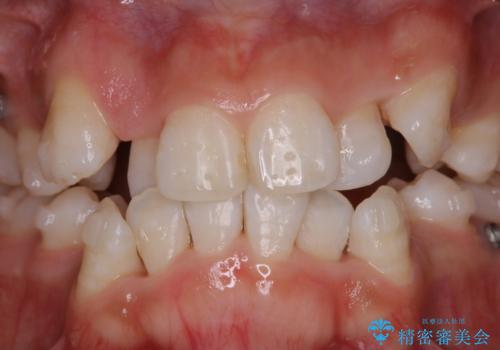

またPMTCを行うことで、ご自身本来の歯の色になり自然な明るさになります。

口元が自然な明るさになることで、より清潔感のある印象になるため結婚式・行事やイベント前などにもPMTCを行うはおすすめです。